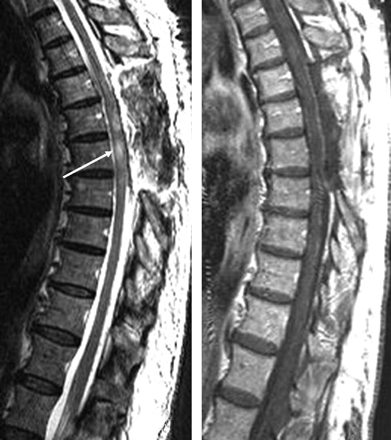

Progressive worsening of the gait impairment and sensitive deficits were noted, and surgery was performed again 10 months after the first surgery. Perimedullary tumor not attached to the spinal cord was again found. Histologic examination confirmed an ependymoma, WHO grade II. The immediate postoperative MR imaging (Fig 6) showed complete macroscopic removal of the lesion.

Sagittal T2-weighted (A) and T1-weighted gadolinium-enhanced (B) images obtained after a second surgery showing the total removal of the anteriorly located cystic lesion. Persistent spinal cord hypersignal intensity is seen in T2-weighted image (arrow).